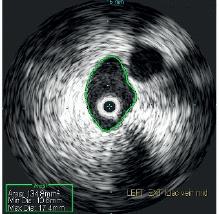

Evaluation of the central veins in the pelvis with venogram revealed no focal iliac vein stenosis or filling defect, and there were no cross-pelvic or lumbar collaterals noted. IVUS with the Visions .035 system was performed, identifying a severe cranial external iliac vein (EIV) stenosis (73%), compared to the normal suprainguinal caudal EIV, due to a non-thrombotic iliac vein lesion (NIVL). Normal suprainguinal caudal EIV and severe cranial external iliac vein stenosis (see Figures 4 and 5)

Post-angioplasty and stent, there was no